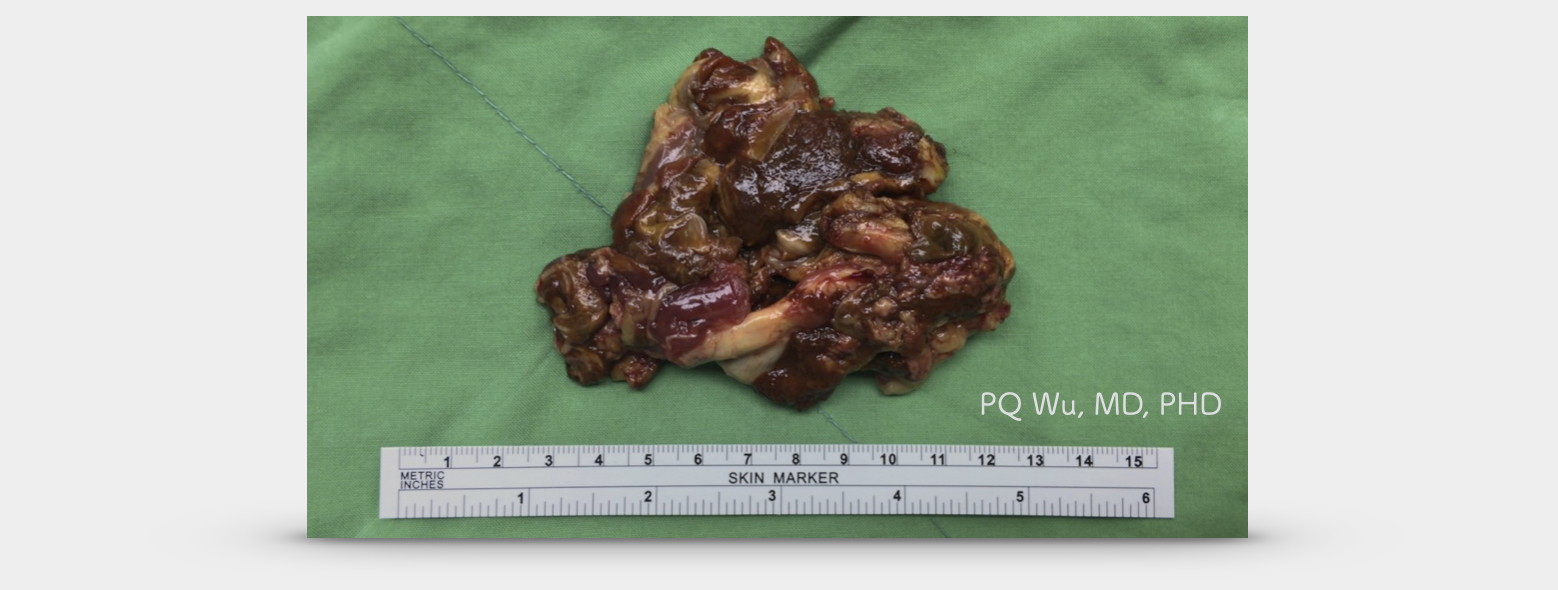

腱鞘巨細胞瘤為帶著血色、咖啡色的纖維型態,部分地方比較摸起來較為扎實,部分地方則是軟軟的結構。

30歲女性,右膝色素絨毛結節性滑囊炎

38歲男性,右膝色素絨毛結節性滑囊炎